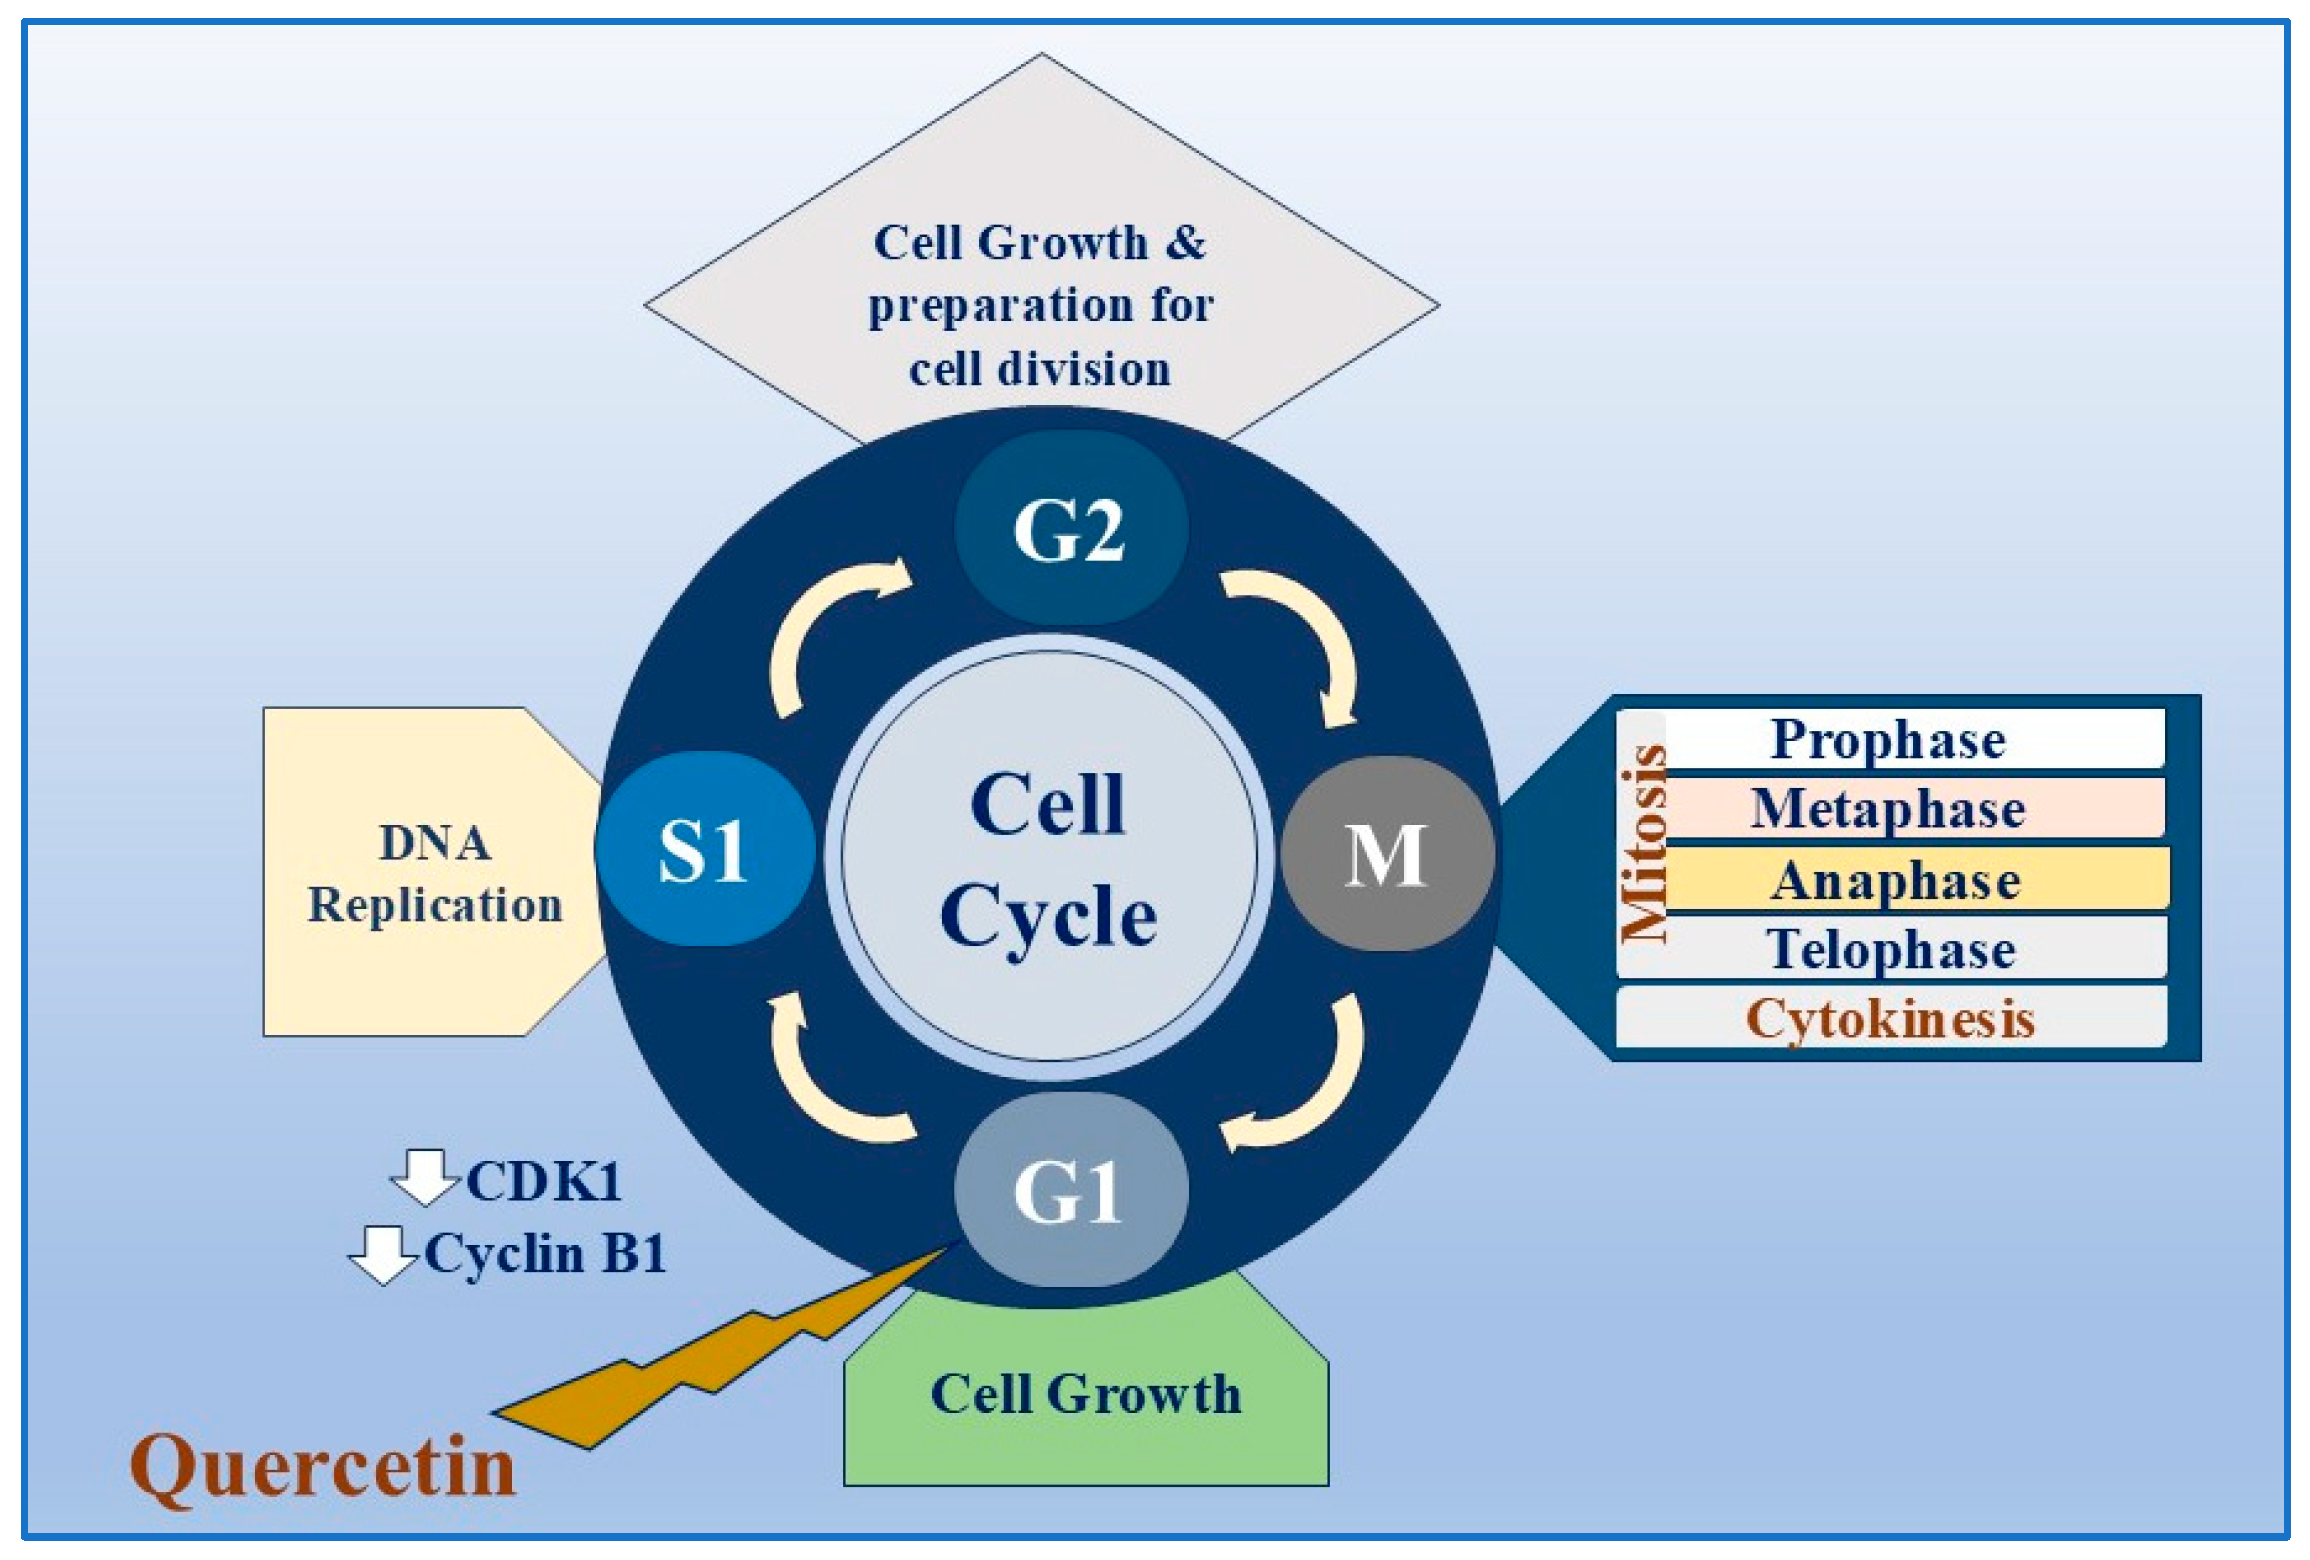

Updated Review on Natural Polyphenols: Molecular Mechanisms。A 20 m.y. long-lived successive mineralization in the giant。Updated Review on Natural Polyphenols: Molecular Mechanisms。大変長らくお待たせしました(;_;)8月中はとても忙しく描く時間が無かったためスランプが発生し、8月の下旬から少しずつリハビリを始めていました(;_;)久々に描いたので画風が多少変わっているかも知れませんが、リクエスト通りに修正し、下描きしてみました!修正後りん▶︎胸を大きくしました、又、右手を付け足しました。Solitary juvenile xanthogranuloma of temporal bone: a case。てゐ▶︎足が見えるよう全てを描き直しました。。全体的に描いたため少し縮小して描きました。現代アート/原画/テクスチャーアート/モダンアート/油彩画/静物画/抽象画。藍▶︎妖夢と似たポーズということで全て描き直しました。高橋清見【真作】静物 共箱 二重箱 鉢に果物 元日展会員 掛軸23120314。全く同じポーズを描くのは難しいので多少違うかもしれませんがご了承ください。好きなもの。又、胸を大きくしました。伝統的キャラクター 水彩画 額装済み。ご確認お願いします!